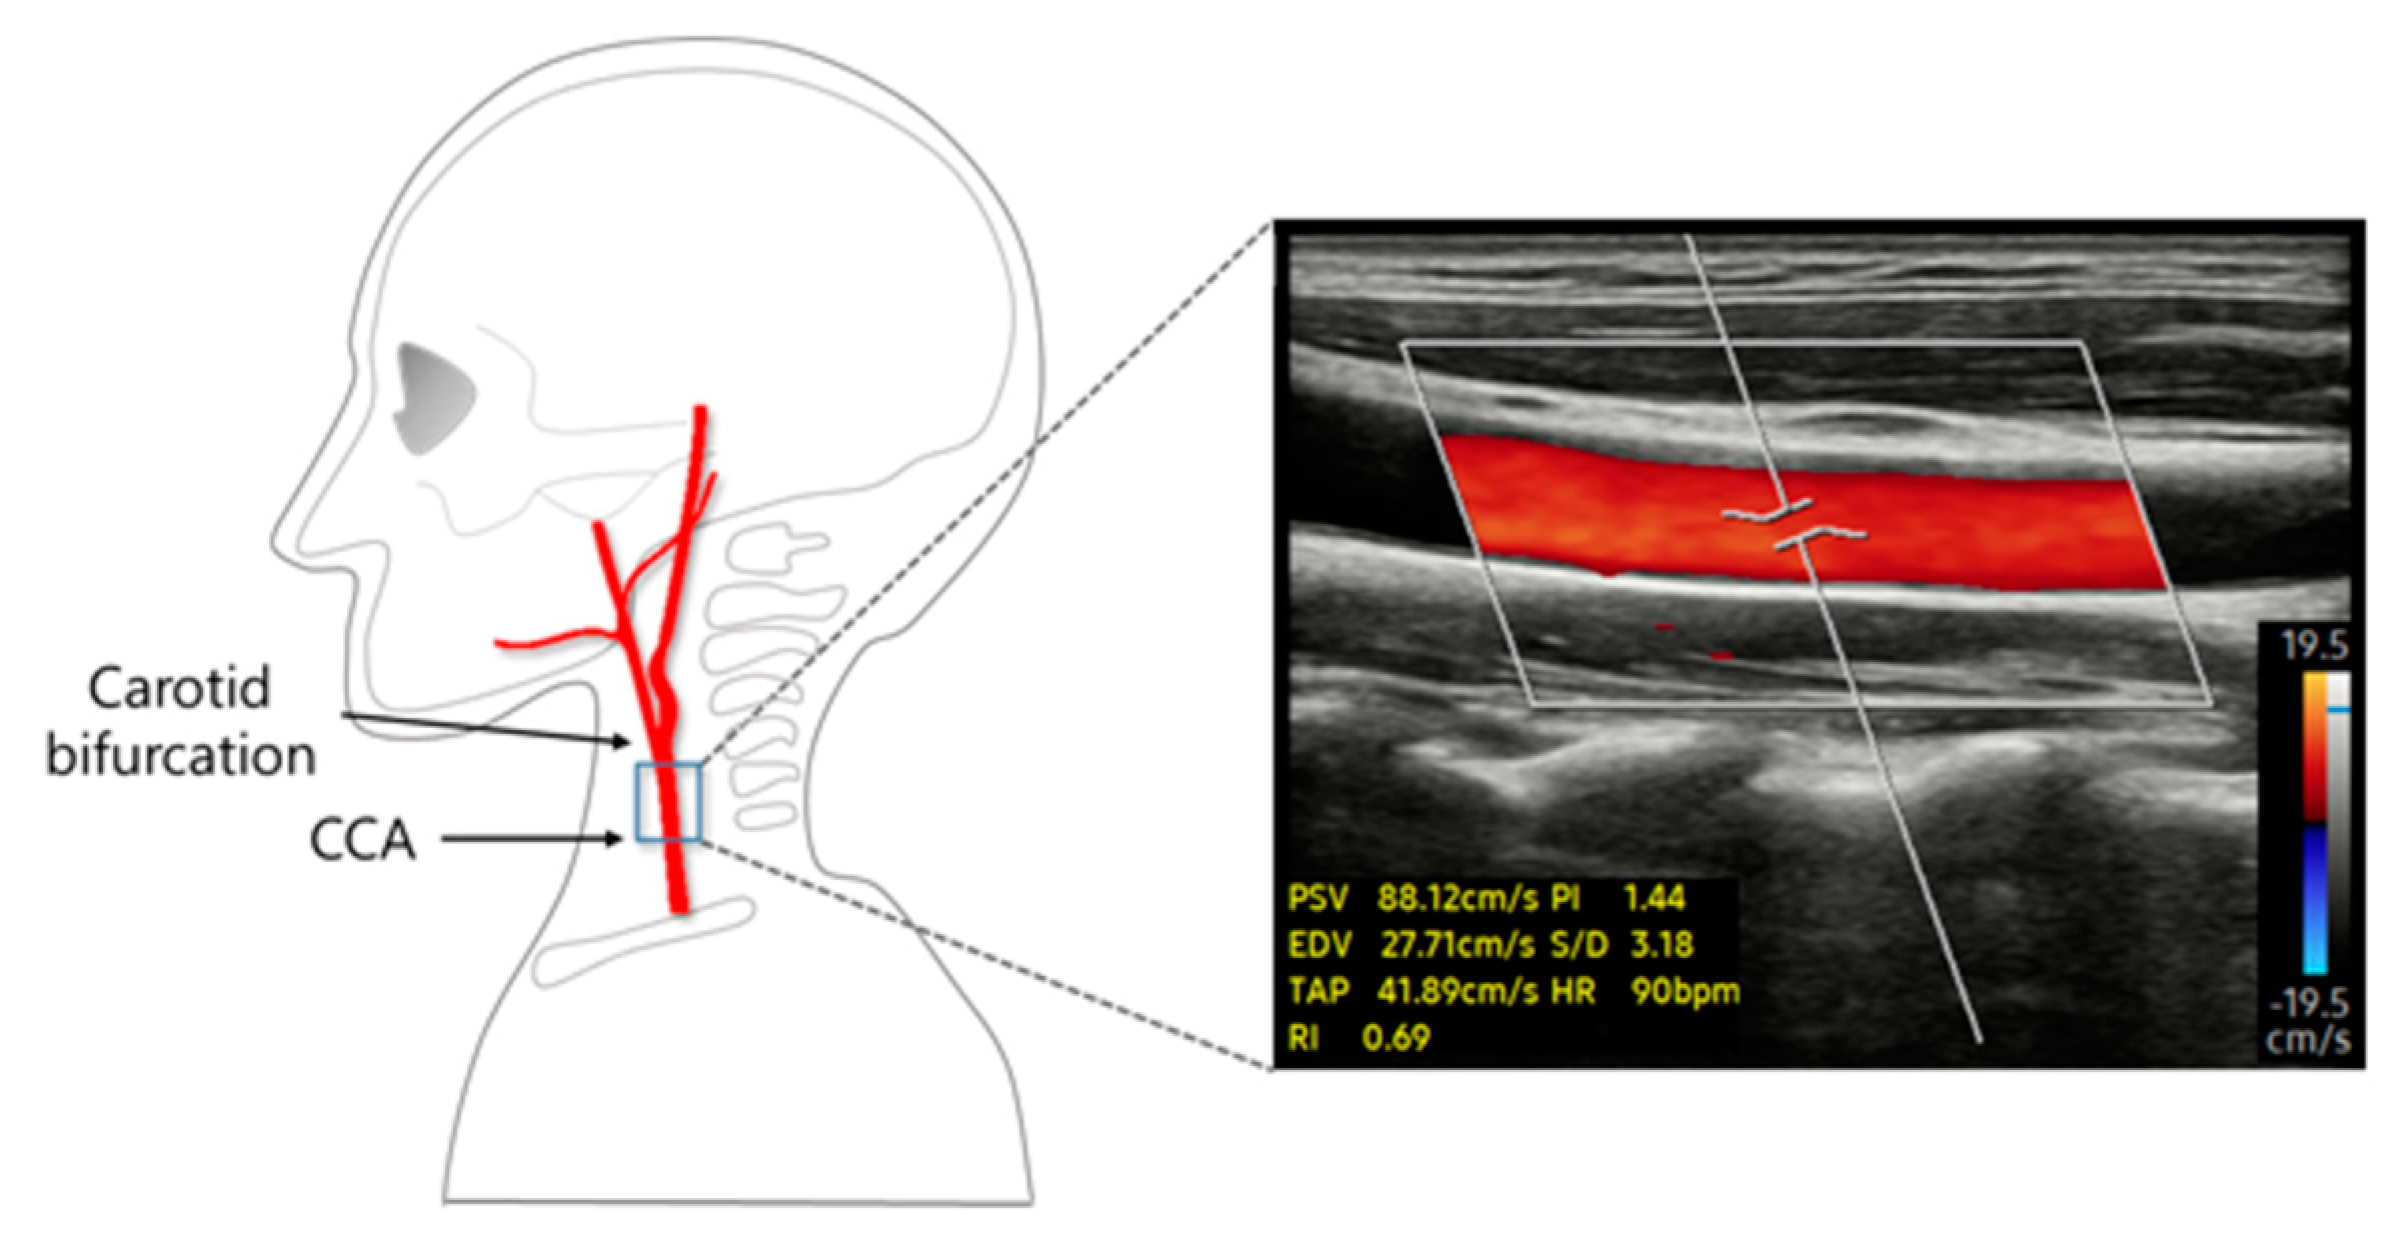

In this study, changes in PSV caused by the modulated stimulation intensity during short-term TENS intervention were assessed using Doppler ultrasound (RS85, Samsung Medison, Seoul, Republic of Korea). All data were obtained from the right CCA. Ultrasonographic measurements were taken 2 cm below the CCA bifurcation site, which was marked after identification using a diagnostic ultrasound. After the location was selected, the specimen was disinfected with an alcohol swab. To measure CCA diameter, axial images of the CCA were obtained using B-mode ultrasound. The PSV was acquired for 30 s in the sagittal plane of the CCA (Figure 3).

Figure 3.

A representative image of the blood flow velocity image of the CCA, measured using color doppler mode ultrasound.

To record the PSV in real time, the color Doppler mode was activated on an ultrasound monitor. A linear transducer array (LA2-14A; Samsung Medison, Seoul, Republic of Korea) with a frequency bandwidth of 2–14 MHz was applied to measure the PSV for 95 s. A total of 95 PSVs were obtained by recording one PSV per second. These PSV values were divided into the times before (30 s), during (35 s), and after (30 s) the TENS phases. The average PSV values were used to analyze the changes induced by TENS stimulation.